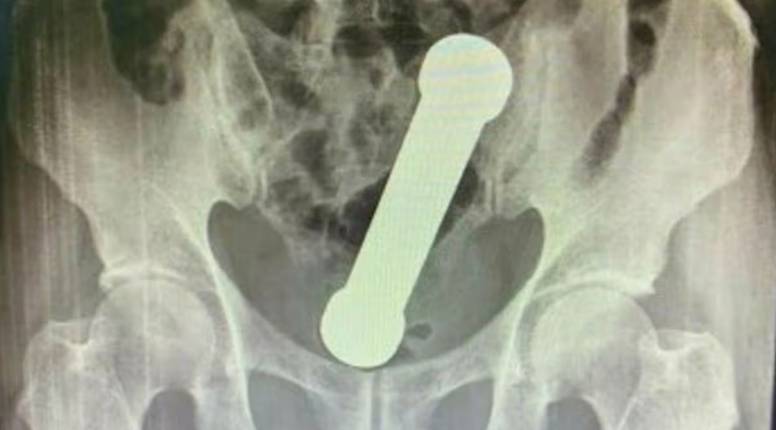

Uslijedio je rektalni pregled, tijekom kojeg, kako se navodi u medicinskom izvješću objavljenom u časopisu Science Direct, "pacijent nije surađivao". Zbog toga su liječnici zatražili rendgensko snimanje abdomena, koje je konačno otkrilo uzrok tegoba - komad opreme za vježbanje dugačak dvadeset centimetara.

Liječnici u Brazilu ostali su zapanjeni kada su primili pacijenta s metalnim utegom od dva kilograma zaglavljenim u rektumu. Pedesetčetverogodišnji muškarac potražio je pomoć tek nakon dva dana neuspješnih pokušaja da samostalno izvadi predmet. Muškarac se javio u bolnicu u Manausu, na sjeverozapadu Brazila, žaleći se na grčeve u trbuhu, mučninu, povraćanje i nemogućnost obavljanja nužde koja je trajala otprilike dva dana. Uteg, dugačak dvadeset centimetara i težak oko dva kilograma, bio je zaglavljen na prijelazu debelog crijeva u rektum, prenosi Daily Star. Dogodilo se to 2022. godine.

Uteg, dugačak dvadeset centimetara i težak oko dva kilograma, bio je zaglavljen na prijelazu debelog crijeva u rektum...